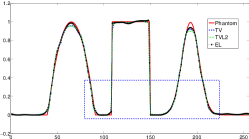

Reconstructed images are presented in Fig. 4. Since CGLS-TV- reconstruction might look more appealing than CGLS-EL we also show the surface representations of reconstructed images (see Fig. 5) and horizontal middle cross-sections (see Fig. 6).

One can notice that CGLS reconstruction is very noisy. CGLS-TV method better suppresses noise, however smooth features are strongly affected by the “staircasing” effect. CGLS-TV- method provides reconstruction with smoother features and CGLS-EL method resolves smooth features even better (e.g. cone-shaped parabola). Although CGLS-EL method performs very well for smooth objects one can notice the wave-like variations of intensity in the background and also at the top of the rectangle (see Fig. 6). This issue can be explained by the properties of our regularizer, in contrast to TV, our penalty does not seek the sparsest solution and does not penalize strongly (pushing to the constant value) a small intensity perturbations. The EL term tends to preserve all sharp edges while uniform noise is smoothed isotropically with the Laplacian. In Fig. 6 one can see that the CGLS-EL method provides better recovery of smooth features while slightly higher (compare to TV and TV-) perturbations visible in uniform areas (the top of the rectangle), however, the edges of the rectangle are defined sharper with the EL penalty.

After estimation of regularization parameters we performed twenty reconstructions for each method with various Poisson noise distributions. The mean values for GR and BR over all noise realizations are shown in Fig. 9. This result proves that the EL penalty is very successful in resolving smooth features (six Gaussians in this case) and also quite competitive for the BR (lower RMSE value than for TV).

In Fig. 10 and 11 one can notice that the BR is very smooth for TV and TV- penalties and some long-wave oscillations can be seen in the reconstructed image with EL penalty. This result corresponds to the expected behaviour of the EL penalty. We note here that the phantoms background (see Fig. 7) is not as flat as TV and TV- penalty recovered it. Furthermore, a small size dot-like feature (approximately in the centre of the phantom) is almost smoothed out with TV and TV- recovery. However, it is visible and well recovered with EL penalty. The sharp features, overall, are reconstructed very well with MLEM-EL method and seem even sharper compare to other methods (see the bone outer rim in Fig 10).